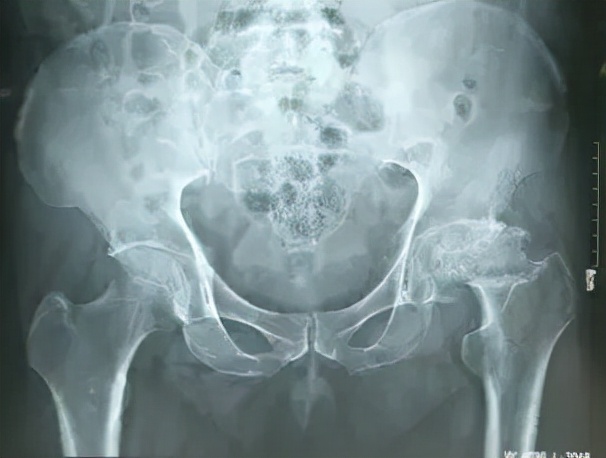

X线平片: 作为主要的诊断手段在股骨头坏死的诊断中仍有不可替代的作用。

股骨头血液供应中断后12小时骨细胞即坏死,但在X线平片上看到股骨头密度改变至少需要8周或更长时间。

x线平片体位主要包括正位及蛙式侧位,蛙式侧位可补充显示正位片的重叠部分。